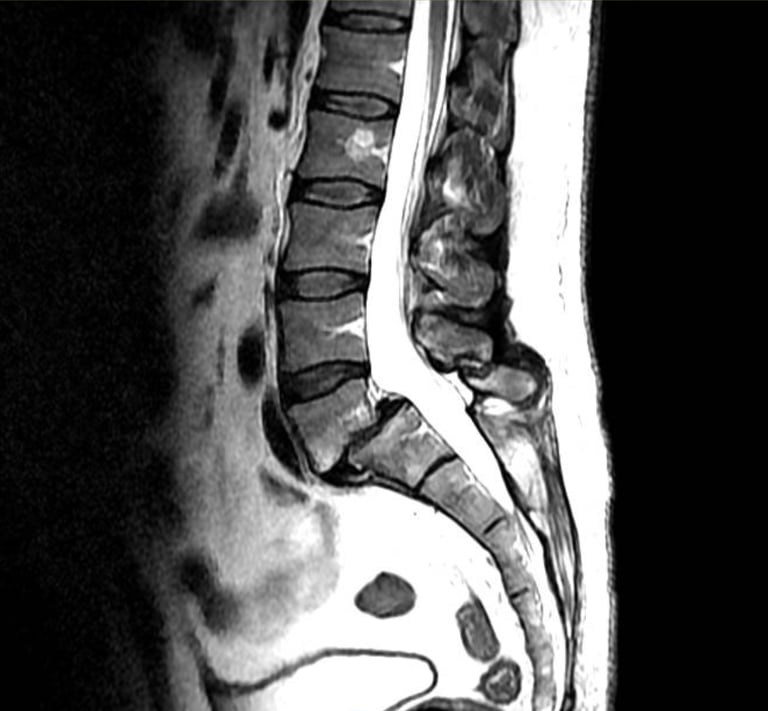

Columna lumbar

Ciática.

Lumbalgia.

Hernias de disco intervertebral.

Espondilolísis.

Espondilolistésis

Escoliosis.

Tumores de columna lumbar.

Escoliosis degenerativa del adulto mayor.

Fracturas traumáticas y patológicas.